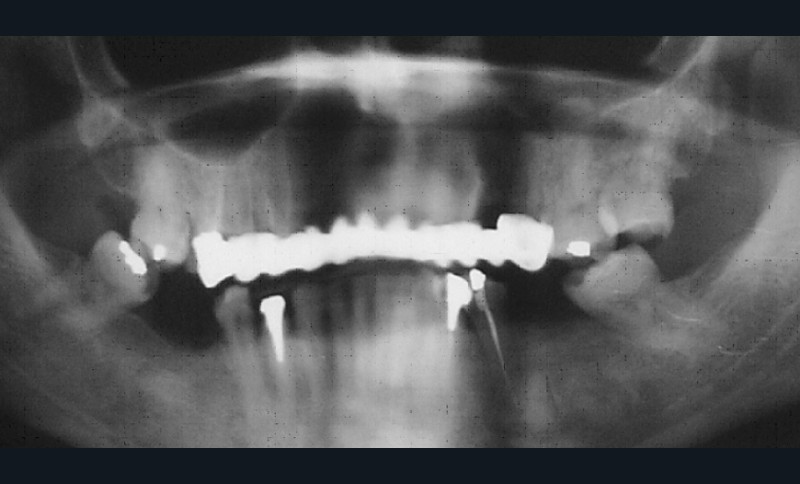

- Examen radiographique : l’orthopantomogramme ne révèle aucune lésion apicale (fig. 6). Les traitements endodontiques semblent corrects. Des ancrages corono-radiculaires sont visibles sur 34 et 44.

La collecte des données physiques et complémentaires révèle, au maxillaire, l’existence d’un édentement de classe III Kennedy-Applegate, modification 1 (antérieure) et un important délabrement coronaire de la 15, 13, 23, 24 ; à la mandibule, la présence d’un édentement de classe III Kennedy-Applegate, modification 1.